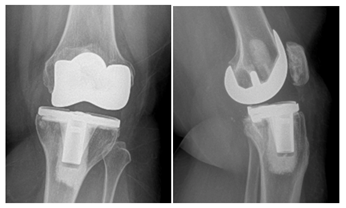

Prior to the patient’s chosen surgical date, she twisted her leg, felt a shift in her knee, and had severe pain along with the sensation her knee being locked (Figure 5).

She was taken to the operating room the following day. Her polyethylene was found in the suprapatellar pouch with damage particularly to the posterior medial region (Figure 6). The tibia tray was found to be well fixed but was found to be fractured in the posterior medial corner (Figure 7). Both component revision was undertaken using Zimmer® NexGen® RH knee with cemented stems as well as a trabecular metal femoral cone in the metaphysis (Figure 8).

Figure 5 AP/Lateral Left Knee showing metal on metal articulation of the femur on the tibia, disengaged polyethylene in the suprapatellar pouch as well as fracture of the posterior medial corner of the tibia tray.

Figure 8 AP/Lateral femur/Lateral tibia of the left knee following revision to a rotating hinge knee with cemented stems and femoral metaphysical cone.